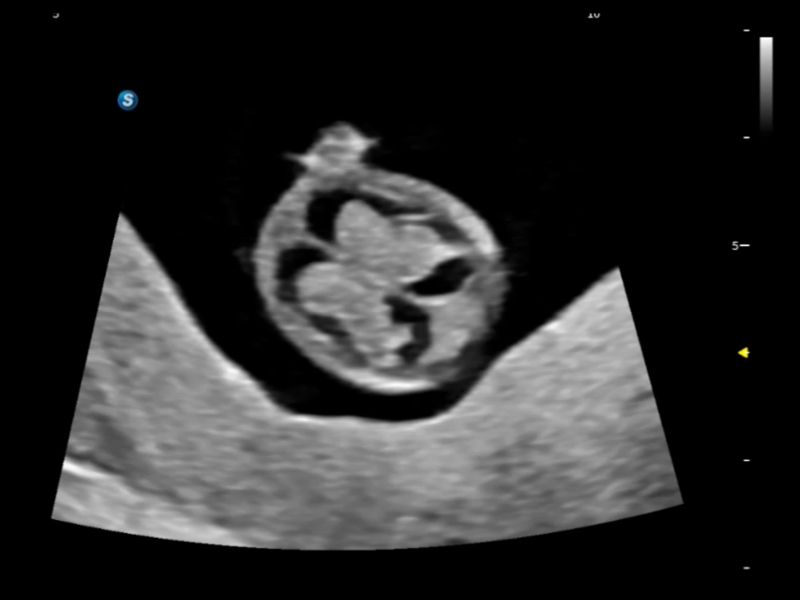

S-Fetus? 鳳眼

胎兒顱腦融合

時(shí)間空間相關(guān)成像

S-Fetus? 鳳眼(A4C切面)